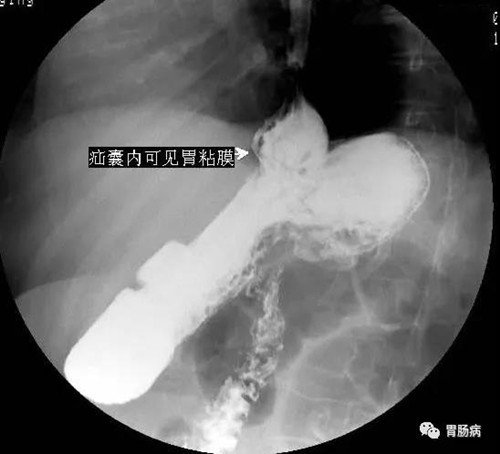

今年60歲的王阿姨有個燒心、反酸的老毛病,有時伴有吞咽困難、胸痛、飯后吐酸水等癥狀,很多大夫都認為是胃食管返流病,但是,醫生開了一大堆胃藥,吃了效果總是并不明顯,反酸燒心搞得王阿姨夜不能寐,苦不堪言。

前幾天,王阿姨感覺癥狀有所加重,來到我們科進一步檢查,于是讓她做了消化道造影,原來王阿姨得了一種吃藥治不好的病:叫食管裂孔疝的病。